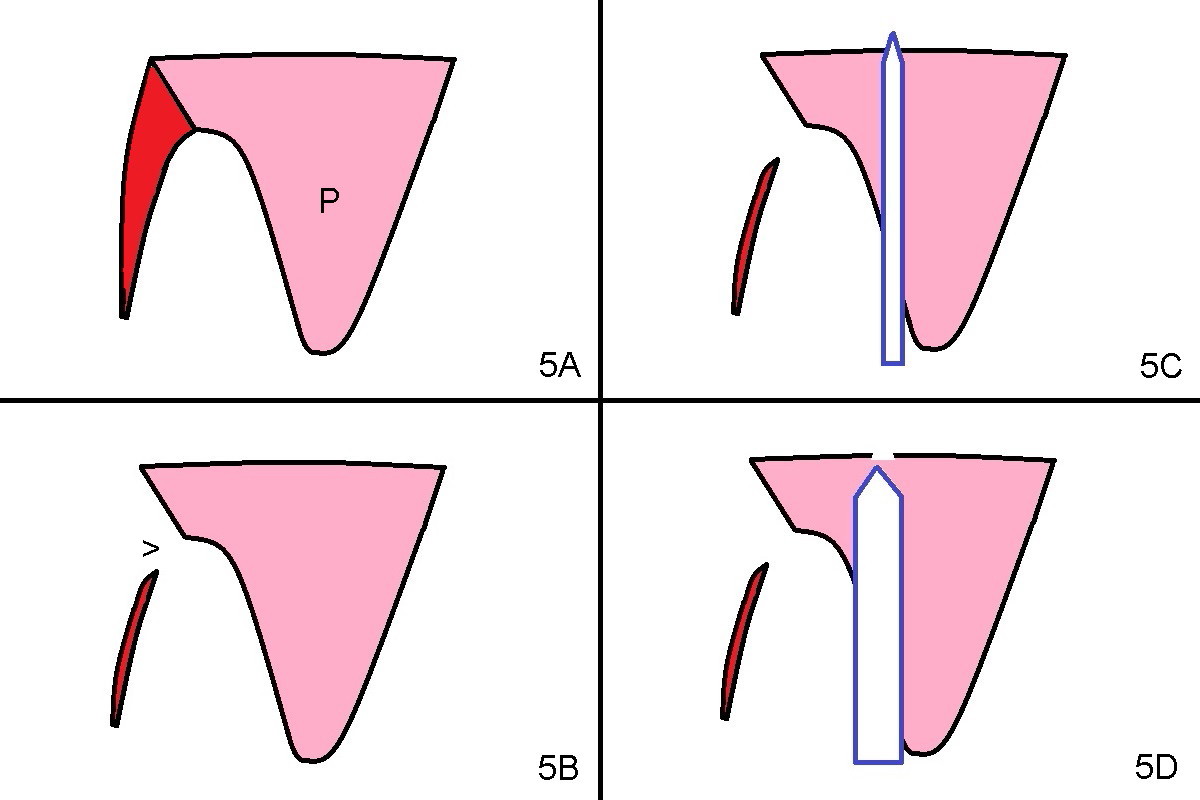

The buccal plate of the socket of #4 is thin and short (Fig.1, 5B (coronal section of the socket) red area) with apical perforation (Fig.5B >). Osteotomy at #4 starts with 1.6 mm drill in the palatal slope (Fig.2 circle; Fig.5C blue arrow), while that at #5 with Magic Split (Fig.2 black line). In fact sinus perforation occurs with the 1.6 mm drill. Osteotomy increases by using Magic Drills sequentially (2.8 and 3.3 mm) at #4 and Magic expander (3.0 mm) and the same Magic Drills at #5 (Fig.3). A 4x11 mm dummy IBS implant is placed with insertion torque of 45 Ncm at #4 with apparently intruding into the sinus (Fig.3). When a 4.5x9 mm implant is placed, the insertion torque is actually reduced (<35 Ncm, Fig.4). As osteotomy or implant diameter enlarges, it shifts buccally with less bone contact buccally (Fig.5D, as compared to Fig.5C)). In brief, once a dummy implant has achieved a reasonably high stability, do not over seat it. A small immediate implant may have more solid bone contact.